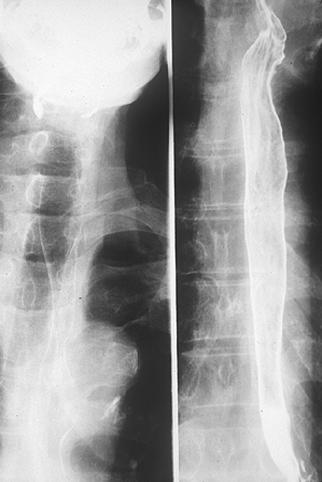

疾患(病理主体)の分類悪性上皮性腫瘍/扁平上皮癌

部位(臓器別)食道/中

検査方法X-P

腫瘍の肉眼分類0型(表在型)/IIc型(IIc+IIb)

病変の最大径(ミリ)40以上

腫瘍の深達度mm